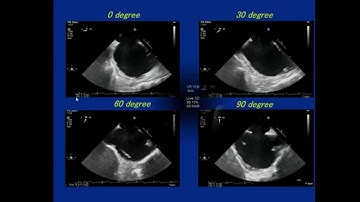

ASD in 3D, part 3